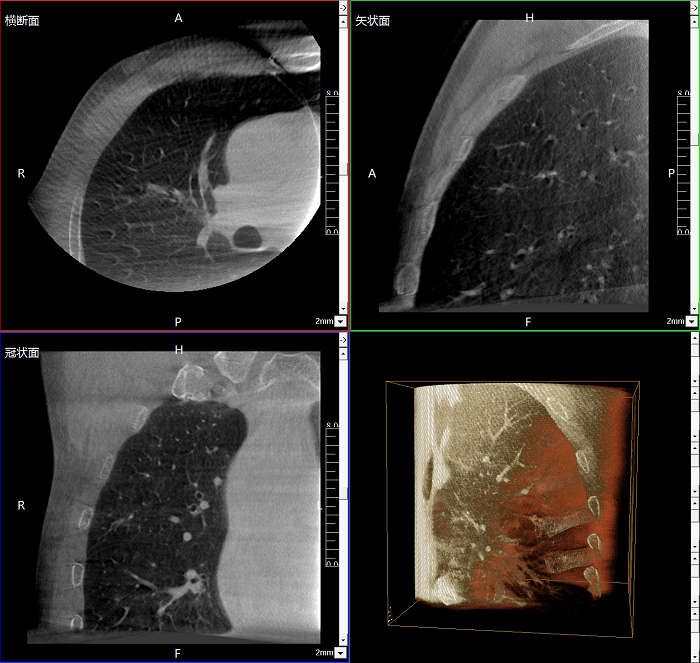

該設(shè)備可進(jìn)行快速的術(shù)中三維掃描,生成類CT斷層圖像和立體3D圖像,保障植入物置入效果。廣泛適用于骨科、脊柱外科、矯形外科、創(chuàng)傷骨科等其他領(lǐng)域。

●極速成像僅需8秒,從數(shù)據(jù)采集結(jié)束到完成三維重建斷層影像